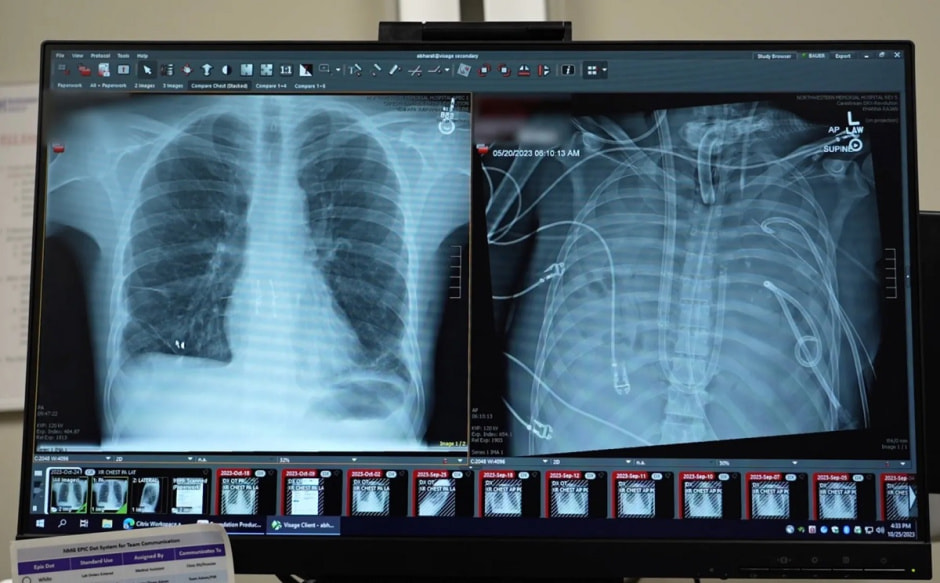

Все началось с тяжелой инфекции: грипп у пациента осложнился бактериальной пневмонией и привел к острому респираторному дистресс-синдрому. Его легкие были полностью разрушены, а состояние осложнилось отказом других органов.

Чтобы остановить распространение инфекции и спасти жизнь, врачи приняли радикальное решение – полностью удалить оба легких.

В течение 48 часов пациент находился без собственных легких, но благодаря технологии его организм продолжал функционировать. За это время состояние стабилизировалось, а инфекцию удалось взять под контроль.

Спустя два дня врачи провели успешную двойную трансплантацию легких.